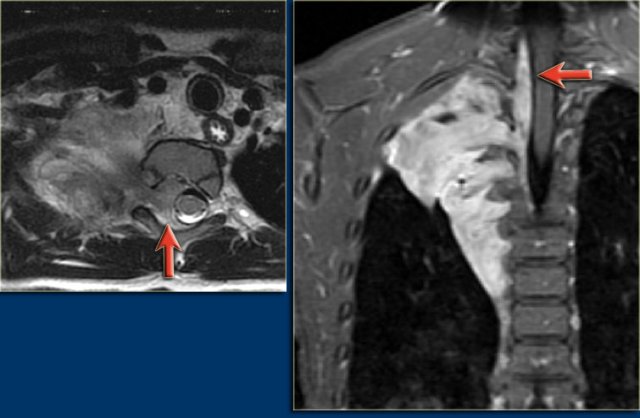

T2 with fatsupression, transversal and coronal T2 with fatsupression, transversal and coronal

MRI may sometimes be used to better delineate the extension of the lesion.

The MRI in this patient shows a cystic mass in the neck extending into the right axilla and mediastinum.

The tumor encases vessels.

The presence of contrast enhancement of the wall or internal septations suggests superimposed infection or a hemangiomatous component.